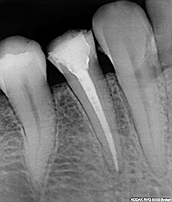

Dişin merkezinden kök ucuna kadar mesafede bulunan sinirlerin alınıp, diş köklerinin içinde bulunan kanalların genişletilip kök ucuna kadar mikroorganizmalardan temizlenmesi ve daha sonrasında genişletilmiş ve temizlenmiş olan kök kanalların doku dostu malzemeler ile doldurulması işlemidir. Bu tedaviden sonra dişin görünen kısmındaki kalan madde miktarına göre hekiminizin uygun gördüğü dolgu, porselen kaplama, porselen dolgu gibi restorasyonlar yapılır ve dişin hem estetik hem de fonksiyonel olarak devamlılığı sağlanır. Kanal tedavisi öncesi muayene önemlidir ve tespitte bulunurken genellikle radyolojik olarak ta değerlendirmek gerekmektedir.

Dişten alınan detaylı röntgen (periapikal) ile kök ve çevre dokular değerlendirilir. Bundan sonra ağız içi muayenede dişte var olan soğuk sıcak hassasiyetleri değerlendirilir ve tedaviye karar verilir. Dişin canlı olup olmadığı tedavinin seyrini etkilemektedir.